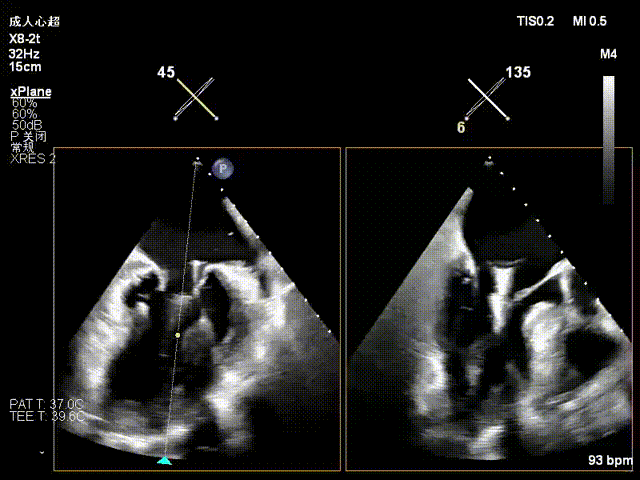

一夹后图像,残余反流位于2区

跨瓣器避过一区夹子,再次跨瓣进入左房

16F鞘送入左房

在左房打开上夹,调整好位置角度后在左室打开下夹

确认夹子位于反流区